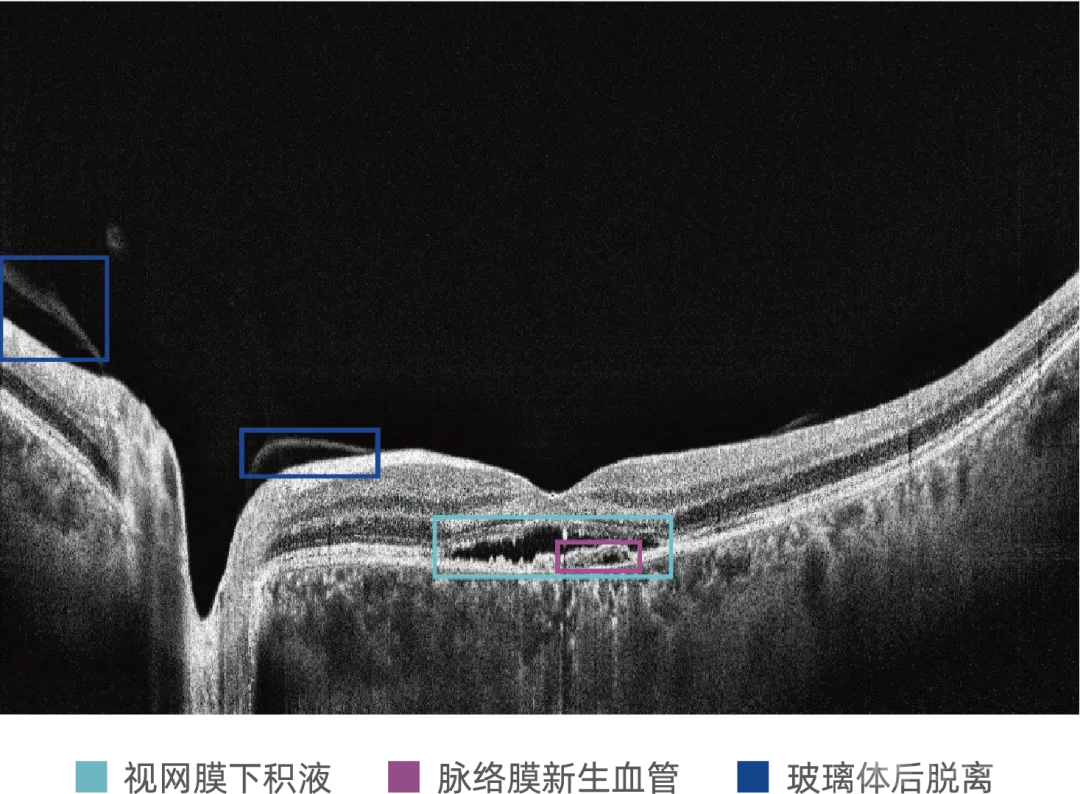

眼科光学相干断层扫描(OCT)影像为眼底三维图像,可清晰呈现视网膜与脉络膜的层次结构及三维形态特征,为精准诊断年龄相关性黄斑变性(AMD)等眼底疾病提供关键形态学依据,是眼科医生重要的临床诊断工具。目前行业获批的眼科AI多基于二维眼底彩照分析;OCT三维体数据较二维图像包含更多空间信息,但也带来了更高的计算复杂度和技术挑战。MIAS-3000通过深度学习算法,自动分析OCT切片图像,精准识别玻璃膜疣、积液、新生血管等病灶信息,为50岁及以上患者提供是否存在中期及中期以上年龄相关性黄斑变性的辅助诊断建议。